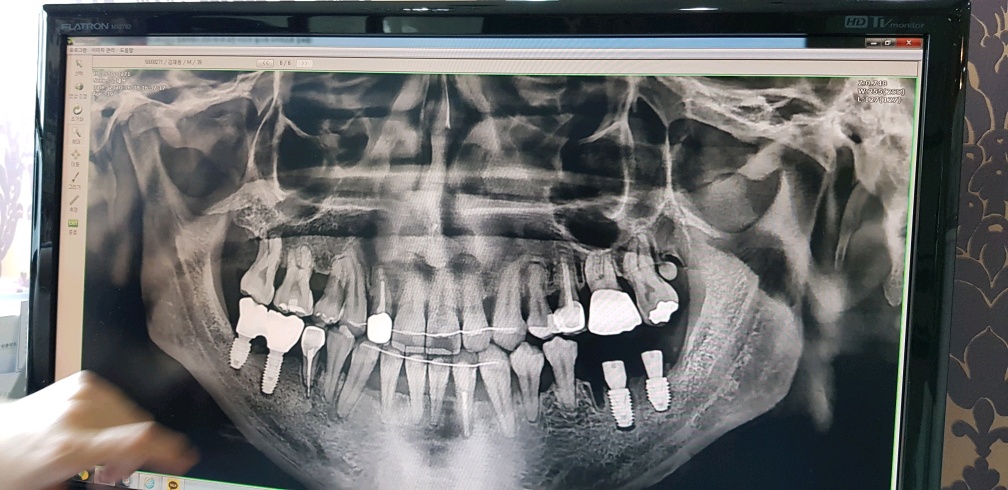

여튼 그렇게 두개의 임플란트를 더 시술하게 되었고 임플란트의 머리부위가(치아색의 구조물)올라가기 전 까진 밑의 유지장치는 본을 못 뜨고 있는 상태였고, 이것 때문에 치아교정 과정이 3달정도가량 더 늦어졌다.

지르코니아 임플란트 4개 + 뼈이식 = 302만원..?

3년6개월에 거쳐 모든 과정이 끝난 지금의 내 치아상태인데

상악은 확실히 바뀐게 보이긴 한다..

그런데 밑의 앞쪽 치아들 중 한 치아는 강제로 이동되서 약간 비스듬히 뿌리가 잡혀있는게 보인다.

아마도 유지장치가 없다면 이 치아가 다시 원래자리로 돌아가겠지...